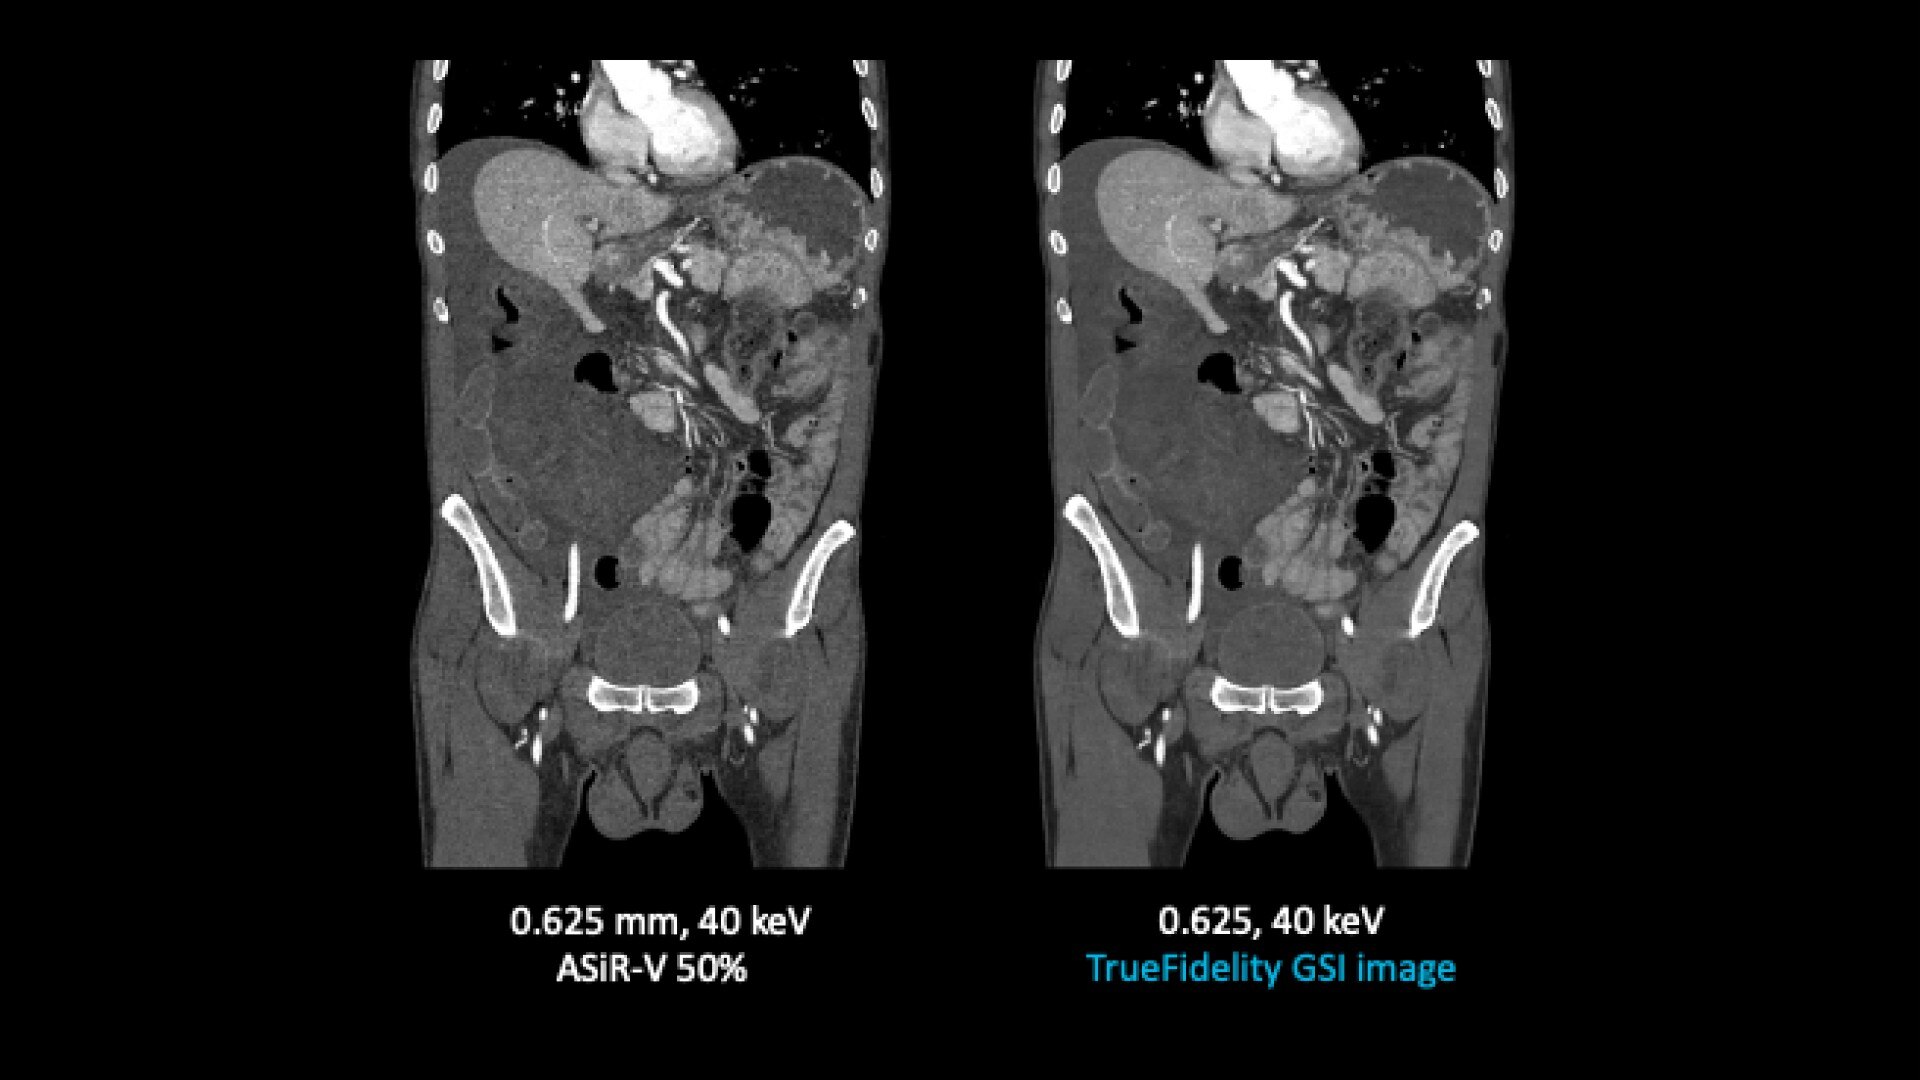

TrueFidelity for GSI now brings the potential to substantially reduce the image noise in all spectral image types

From virtual monochromatic images to material image pairs and virtual non-contrast images, with and without metal artifact reduction. Specifically, reducing the image noise inherent with low keV images resolves one of the traditional technical challenges in adopting more dual-energy protocols across the full patient population.